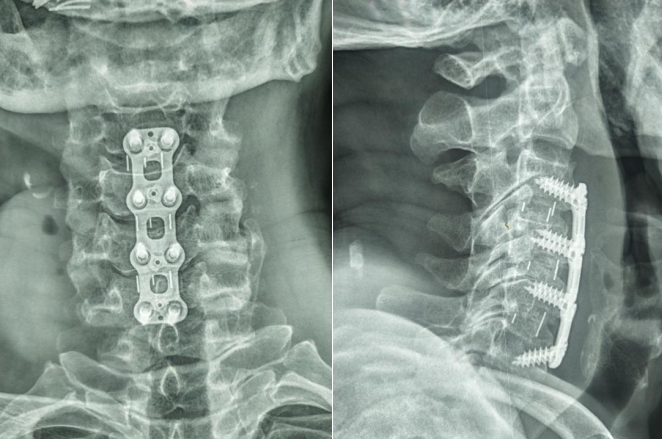

近日,大竹县人民医院骨科团队顺利完成了一例多节段颈椎ACDF手术,手术全程仅用2.5小时,顺利救治了一名因颈脊髓损伤伴不全瘫痪的患者。

据悉,患者肖某现年75岁,“颈部摔伤伴四肢麻木乏力3小时”入院入院时四肢肌力明显减弱约2级,感觉麻木,痛觉减退,呈不全瘫痪状态,经检查诊断:1颈脊髓损伤伴不全瘫痪;2、颈椎间盘突出伴椎管狭窄。颈脊髓损伤是一种非常严重的损伤,造成患者死亡或残疾的几率较大,为挽救患者生命,骨科团队根据患者情况,为患者制定了“多节段颈椎ACDF手术”的方案。经术前充分准备骨科团队通过紧密协作,仅用2.5小时顺利完成多节段颈椎ACDF手术。术后在护理团队的精心护理下患者恢复良好,目前四肢肌力达4级,麻木减退,已能够逐渐下床行走。